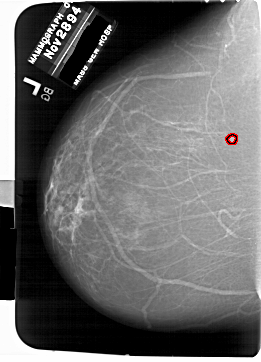

A_1769_1.RIGHT_MLO

RIGHT_MLO LINES 6871 PIXELS_PER_LINE 4966 BITS_PER_PIXEL 12 RESOLUTION 43.5 NON_OVERLAY